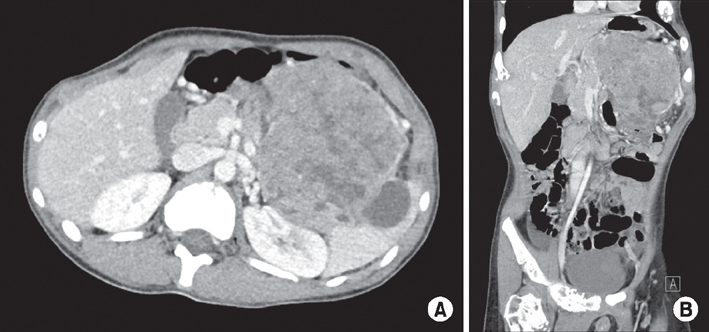

The patient started a standard diet 9 days postoperatively and was discharged the following day. Pathological diagnosis of the tumor determined a mitotic count of 50 cells/10 HPF; 30% of the tissue was necrotic, and the tumor cells were positive for chromogranin A and synaptophysin, which supported the final diagnosis. Ki-67 proliferative staining was positive in 80% of cells, and the tumor cells were positive for beta-catenin, CD10, E-cadherin, and cytokeratin (

Fig. 2,

3). The final pathological diagnosis was mixed acinar-endocrine carcinoma. The patient is currently undergoing adjuvant chemotherapy with cisplatin, etoposide, and cyclophosphamide in our pediatrics department; the regimen of chemotherapeutic agents used was based on the standard regimen used to treat pancreatoblastoma.

Fig. 3Immunochemical staining of the biopsy specimen. Chromogranin A (×100) (A), synaptophysin (×40) (B), and E-cadherin (×40) (D) were focally positive, whereas Ki-67 (×40) (C) was positive in 80% of the specimen.